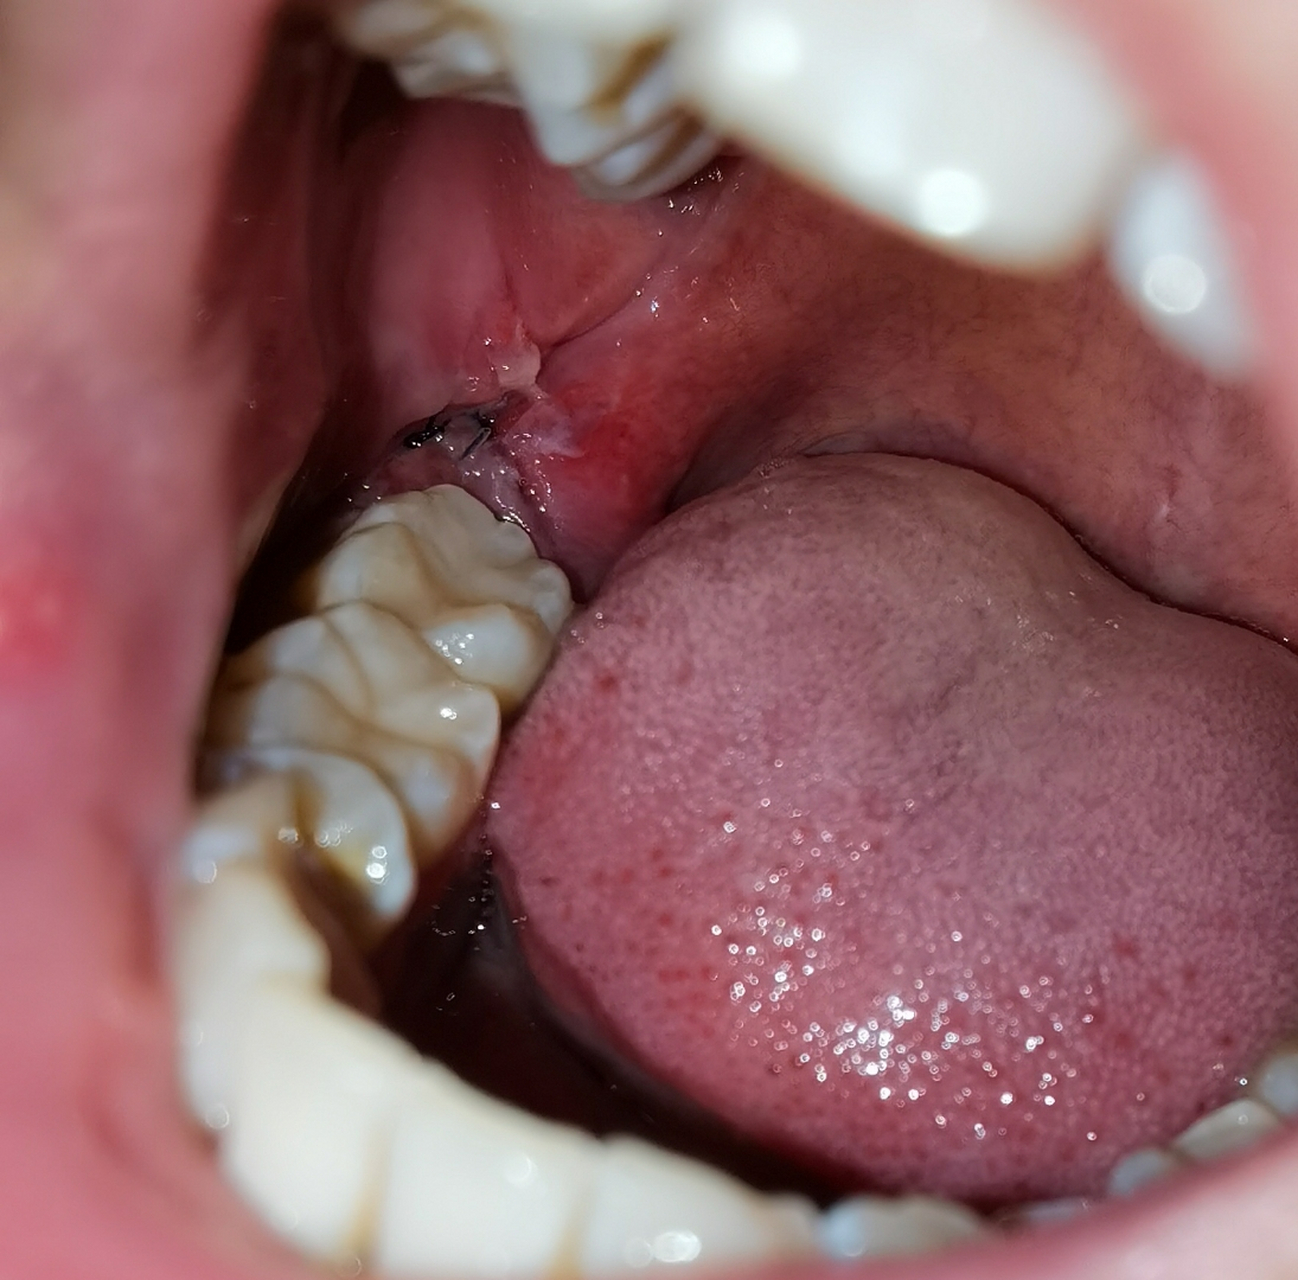

拔牙第四天,看着好恐怖

注意啦!拔牙一周后,牙窝的这种变化要警惕!